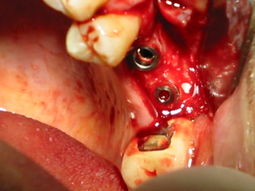

111-1174_IMG.JPG

...il lembo verrà chiuso dopo aver applicato, a copertura della zona di apposizione ossea, una membrana di collagene essiccata riassorbibile...